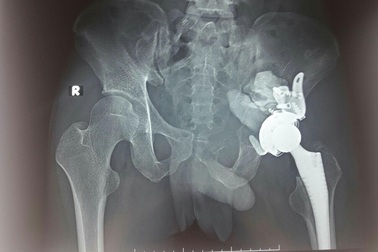

Ngỡ đau khớp hoá khối u hiếm gặpHơn một năm qua, anh Hoàng Đình H. (28 tuổi, Bắc Giang) chịu đựng những cơn đau khớp háng đến mức đi lại khó khăn. Vốn chỉ nghĩ đơn giản bệnh khớp, không ngờ các bác sĩ phát hiện anh bị ổ cối xương chậu hiếm gặp